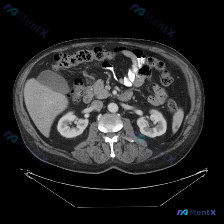

整理了一个很有警示意义的影像读片场景,特别能体现「循证影像诊断」的重要性。 先看「预设问题」与「影像事实」的冲突 预设: 临床/提问指向「图中存在脾脏病变」 影像事实(单帧增强CT): - 扫描层面:仅上腹部,显示肝右叶部分、胆囊、双肾、胰腺、血管、胃及肠管 - 强化状态:增强扫描(血管强化明显),...

看到一个资料,问题直接指向「脾脏病变」,附上了一张腹部增强CT的横断面图像。整理一下读片和分析思路,这个病例的核心其实不是「找病变」,而是「怎么面对阴性结果」。 病例影像基础信息 - 检查手段:腹部CT横断面,软组织窗 - 增强状态:根据血管及实质强化,考虑为静脉期/平衡期 - 扫描层面:上腹部,包...